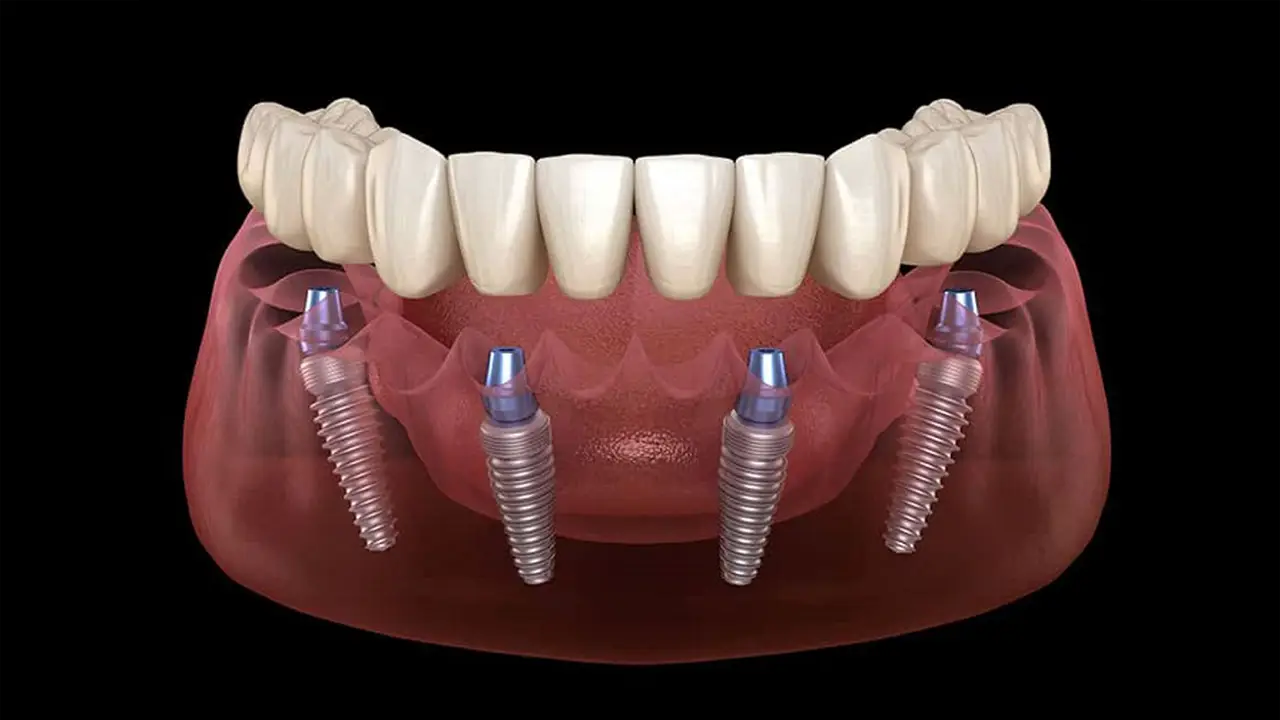

Il carico immediato è una tecnica implantologica che permette di inserire gli impianti dentali e applicare una protesi fissa provvisoria nello stesso giorno.

A differenza delle metodiche tradizionali, che richiedono mesi di attesa, questa soluzione riduce i tempi di riabilitazione e consente al paziente di tornare subito a sorridere e mangiare.

Grazie alla pianificazione digitale e a impianti di ultima generazione, è possibile ottenere stabilità primaria immediata e un’estetica naturale, con un intervento mini-invasivo spesso eseguito in sedazione cosciente.

Ogni intervento viene pianificato al computer. Con software dedicati viene creata una guida chirurgica 3D personalizzata che permette di inserire gli impianti con massima precisione e minimo trauma chirurgico.

Entro 24 ore dall’intervento viene consegnata una protesi fissa provvisoria su misura. Funzionale ed esteticamente naturale, consente di tornare subito alla vita quotidiana senza disagi.

Protesi definitiva

Dopo alcuni mesi, completata l’osteointegrazione, viene realizzata la protesi definitiva in materiali di alta qualità (zirconia o composito stratificato). Il risultato finale è stabile, duraturo e perfettamente integrato con il sorriso.